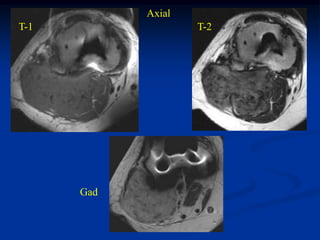

Case #258.4      Axial T-1            T-2

Gad

65 yr old male with painful

mass in buttock for 4 months

Cor T-1   T-2

Sag T-2   Gad